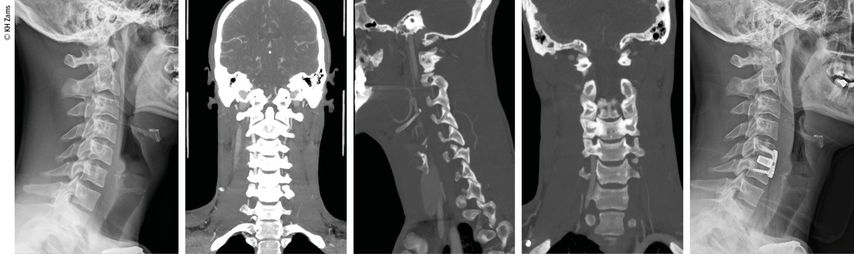

Abb. 2: Fallbeispiel: Mann, 57a, Z.n. Fahrradsturz, stabile Fraktur des Proc. artic. C2 r. mit Dissektion der A. vertebralis r. mit asymptomatischem Substanzdefekt im hinteren Stromgebiet (cMRT), Heparintherapie initial, anschließend APT